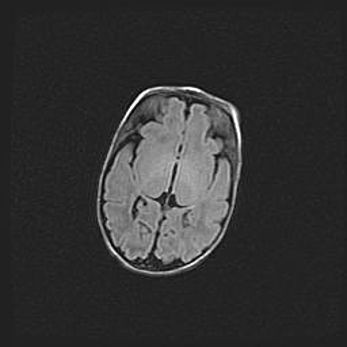

Наружная гидроцефалия с возможной атрофией височных областей.

Возраст: 28 дней

Вес: 3670 г

Пол: мужской

Окружность головы: 38 см

Срок гестации: 40 недель

Гидроцефалия головного мозга у новорожденных – это заболевание, которое характеризуется скоплением избыточного количества спинномозговой жидкости в желудочковой системе головного мозга в результате затруднения её перемещения от места выработки к месту поглощения в кровеносную систему или вследствие нарушения абсорбции. При открытой наружной форме гидроцефалии у новорожденных расширяются и переполняются субарахноидные пространства.

При нормотензивных  формах,  которые,  как  правило,  являются  следствием  перенесенных ишемических  повреждений  паренхимы  мозга,  возможно  сочетание микроцефалии  с нормотензивной гидроцефалией. В основе данных изменений лежит атрофия больших полушарий с преимущественной  локализацией  в  лобно-височных  областях.